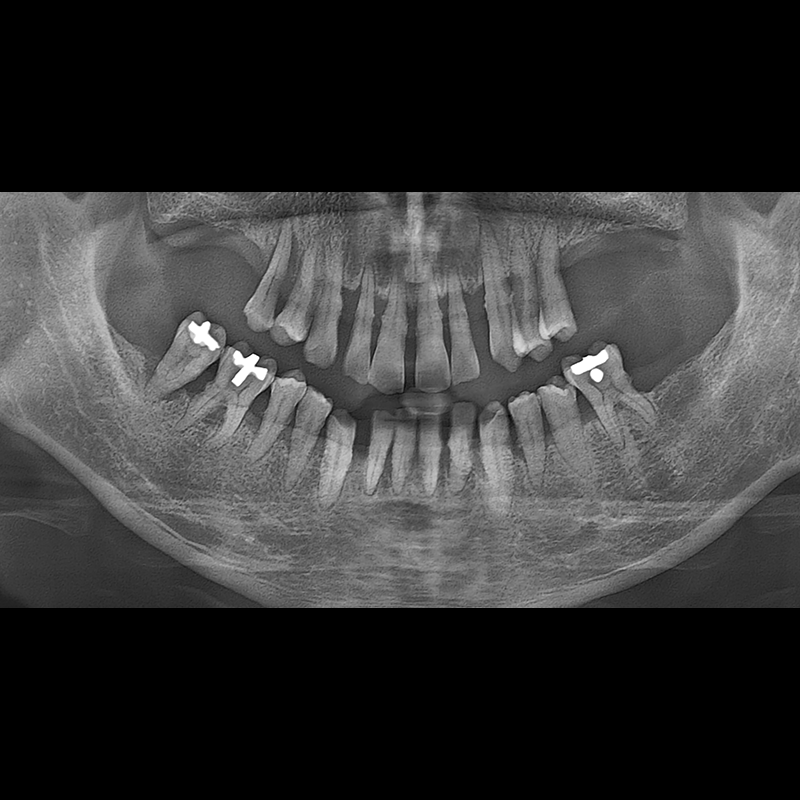

BEFORE AFTER

インプラント手術事例 2025.05.30

欠損した歯の部分と、生かしにくい歯の位置にインプラントを植立しました。